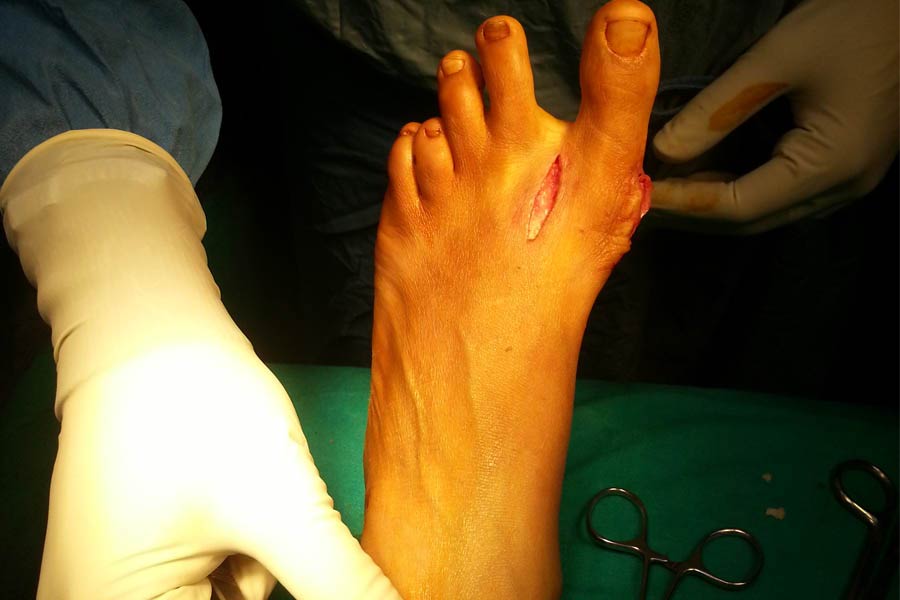

Trauma

Case 1